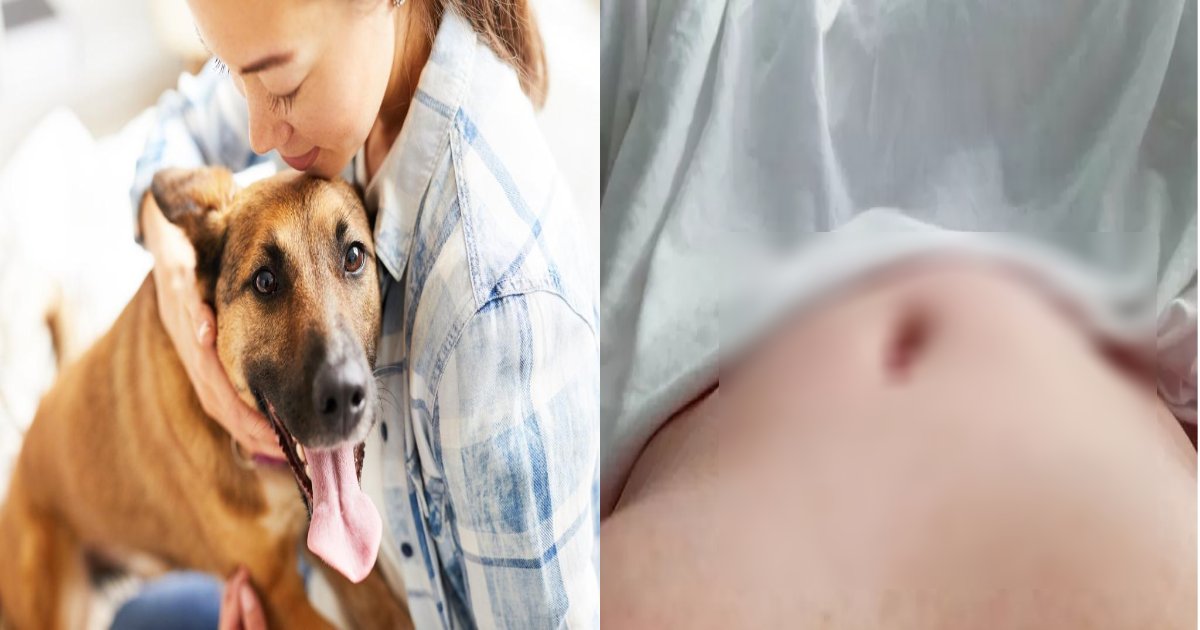

先月31日(現地時間)、イギリスの日刊紙デイリースターは、しきりにお腹の上に上がって脚で撫でてくる愛犬のおかげで「12㎝の腫瘍」を発見した女性の話を伝えました。

イギリス・イングランド東北部のサウスシールズに住む女性、テス・ロビンソン(41)は今年1月、卵巣癌3期の診断を受けました。

単純にお腹の肉が増えたと思っていた彼女の体の中には、なんと12㎝にもなる巨大な腫瘍があったのです。

しかし、体には何の異常もなく、病院に行く予定もなかった彼女が劇的に癌を発見できたのは、ペットのチワワ、ローラのおかげでした。

ところが、ある日からかローラがしきりにお腹をじろじろ眺めたり、お腹の上に上がって脚で撫でるなど異常行動を見せ始めたのです。

最初は大したことはないと思っていた彼女も、ローラが数週間同じ行動をしたので、何かがおかしいと思い、病院を訪れました。

衝撃的なことに、医師は彼女に卵巣癌3期の診断を下し、彼女は直ちに子宮摘出手術と抗ガン治療を受けることになりました。

幸い、厳しい抗ガン治療に耐え抜いた彼女は「ローラがいなかったら、今の私はいなかっただろう」とし「ローラは私の命の恩人だ。残りの人生をローラと一緒に最高の時間する」と愛情を示しました。